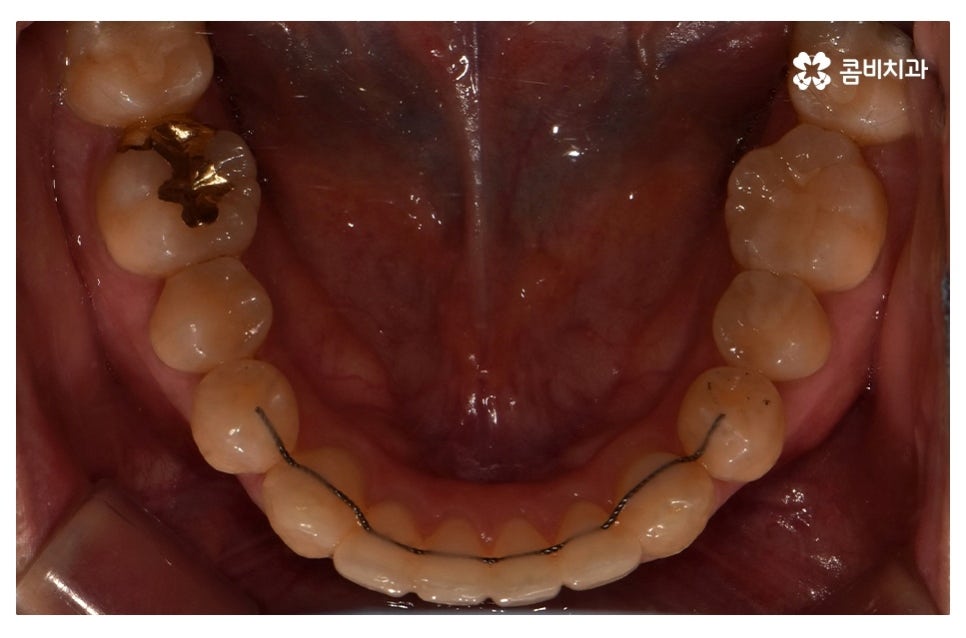

이번 포스팅에서 보인 덧니교정 사례의 경우 기능이 적은 작은 어금니를

발치하여 교정이 진행되었으며 발치를 진행하는 경우

작은 어금니를 발치하는데 충치 등으로 인해 손상이 큰 치아를

발치하는 경우가 일반적이라고 할 수 있어요.

물론 구강 내 치아의 이동 공간이 충분한 경우에는 비발치로도

덧니교정이 진행되는 경우도 있으며 덧니가 심하지 않은 경우에는

부분교정으로 치료가 진행되는 사례도 있어요.

요즘은 교정 장치의 선택에 있어서 다양한 선택이 가능하지만

보편적으로는 본 포스팅의 사례처럼 클리피씨 교정이 많이 선호되고 있어요.

클리피씨 교정은 일반적인 교정보다 치료 기간을 단축시킬 수 있고

통증이 비교적 적으며 세라믹 재질로 심미적이라는 장점이 있어요.

위 환자분의 경우 덧니교정에 걸린 치료 기간은 약 24개월 정도이며

성인 이후에 치료를 진행한 사례라고 볼 수 있어요.